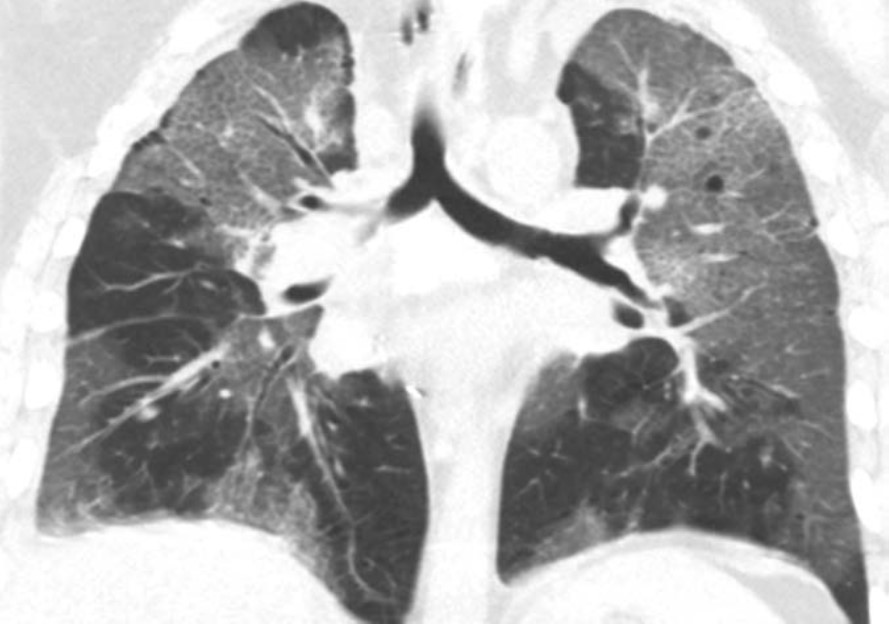

Acute rejection can occur anytime after lung transplant. It consists of two types, acute cellular rejection (ACR) and antibody-mediated rejection (AMR), which can coexist. ACR is the more common of the two types and occurs when recipient T lymphocytes attack donor antigens within the lung allograft. Approximately 35% of lung transplant recipients experience at least one episode of ACR during the 1st year after transplant [2]. During these episodes, patients may be asymptomatic or may present with nonspecific symptoms such as dyspnea and cough. The imaging findings of ACR are nonspecific and include consolidation, ground-glass opacities, and septal-line thickening; as with hyperacute rejection, ACR resembles pulmonary edema. Given its nonspecific clinical and imaging manifestations, ACR requires transbronchial biopsy and tissue analysis for diagnosis. Timely treatment, typically by increased immunosuppression with steroids, is important because ACR is the greatest risk factor for chronic lung allograft dysfunction [4]. Figure 1 shows a patient with biopsy-proven ACR.

Fig. 2—Patient with history of bilateral lung transplant who developed antibody-mediated rejection (AMR), which was diagnosed by transbronchial biopsy and donor-specific antibody blood testing. Chest CT at time of AMR diagnosis shows ground-glass opacities and reticulation in both lungs and small pleural effusions.